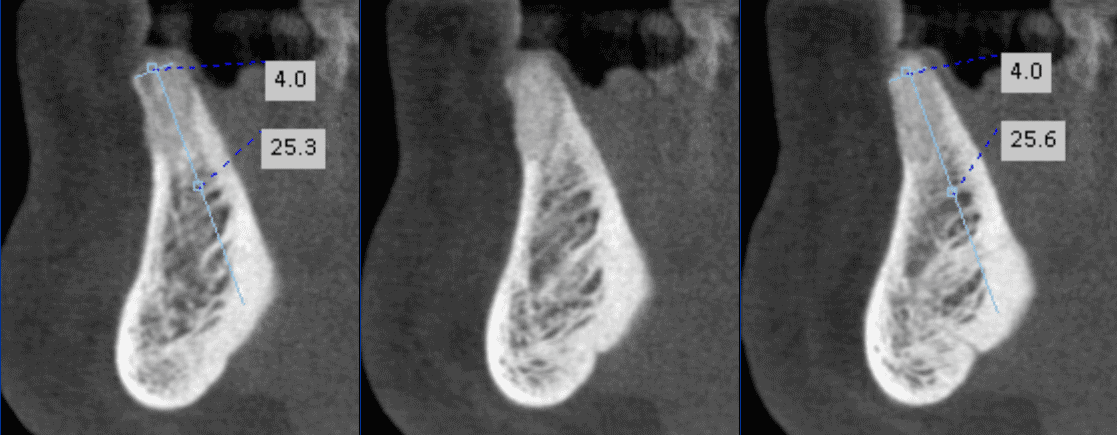

Grafted bone in lower incisor area